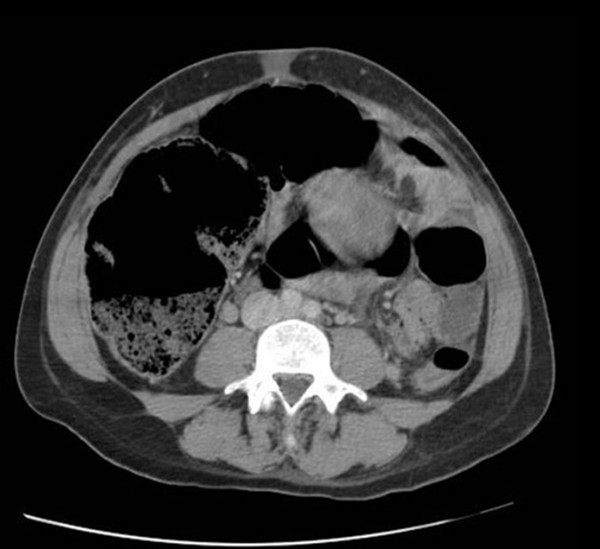

From jetem.org

Ogilvie's Syndrome, CT, Annotated. JETem 2020 JETem Ogilvie S Syndrome Decompression Conservative management involves a trial of bowel rest, nasogastric tube decompression, and rectal tube placement. Decompression of the colon is needed, before the colon dilates beyond a point of no return. It may be managed by addressing underlying conditions (ie,. Mortality rates associated w ith ogilvie syndrome are notably higher when these complications arise. Timely intervention, including deco mpressive pr. Ogilvie S Syndrome Decompression.